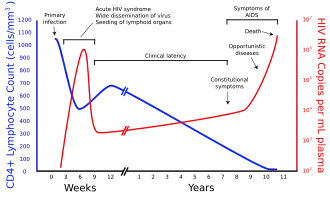

O VIH infecta células vitais no sistema imunitário, como os linfócitos T auxiliares CD4+, macrófagos e células dendríticas.[4] A infeção por VIH provoca a diminuição do número linfócitos T CD4+ através de diversos mecanismos, entre os quais a apoptose de células espectadoras,[5] a morte viral direta de células infectadas, e morte de linfócitos T CD4+ através de linfócitos T citotóxicos CD8 que reconhecem as células infectadas.[6] Quando o número de linfócitos T CD4+ desce abaixo do limiar aceitável, o corpo perde a imunidade mediada por células e torna-se progressivamente mais suscetível a infeções oportunistas.

A maior parte das pessoas infetadas com VIH, quando estão sem tratamento, desenvolve SIDA. A elevada mortalidade desta doença deve-se ao colapso progressivo do sistema imunitário, ao qual está associado o aparecimento de infeções oportunistas ou tumores malignos.[7] Sem tratamento, cerca de nove em cada dez pessoas infetadas com VIH desenvolve SIDA após de 10-15 anos, embora algumas pessoas desenvolvam muito mais cedo.[8] O tratamento com antirretrovirais aumenta a esperança de vida de portadores do VIH, mesmo que a infeção tenha já evoluído para um diagnóstico de SIDA. Com a entrada de novos antiretrovirais a expectativa passou para algo em torno de 20-50 anos (provavelmente, esta expectativa pode ser ainda maior, posto que atualmente há novos medicamentos e terapias mais toleráveis ao organismo dos portadores). Para pessoas com HIV em tratamento antiretroviral de longo prazo e com alta contagem de células CD4, estima-se que a expectativa de vida seja próxima à da população em geral, independentemente de quando iniciaram o tratamento.[9]

A relação sexual é o principal meio de transmissão do VIH. Tanto o VIH X4 como o R5 estão presentes no sémen que é transmitido entre o homem e o seu parceiro sexual. Os viriões podem assim infetar vários alvos celulares e disseminar-se por todo o organismo. No entanto, a existência de um processo de seleção faz com que através desta via seja predominante a transmissão do vírus R5.[36][37][38] A forma como o processo seletivo funciona está ainda a ser investigada, mas um dos modelos propõe que os espermatozoides possam seletivamente transportar VIH R5, uma vez que na superfície possuem CCR3 e CCR5, mas não CXCR4,[39] e que as células epiteliais genitais sequestram de forma preferencial vírus X4.[40] Em pessoas infetadas com o subtipo HIV-1, muitas vezes verifica-se a troca de co-recetor durante a fase avançada da doença, e as variantes T-trópicas aparentam poder infetar diferentes linfócitos T através do CXCR4.[41] Estas variantes replicam-se então de forma mais agressiva e com maior virulência, o que provoca a diminuição acentuada dos linfócitos T, o colapso do sistema imunitário e o aparecimento de infeções oportunistas, características da SIDA.[42] Assim, durante o curso da infeção, a adaptação viral para passar a usar o CXCR4 em vez do CCR5 pode representar um passo fundamental na progressão para a SIDA. Vários estudos em indivíduos infetados com o subtipo B concluíram que 40 a 50% dos pacientes com SIDA podem apresentar vírus T-trópicos e, presume-se, fenótipos X4.[43][44]